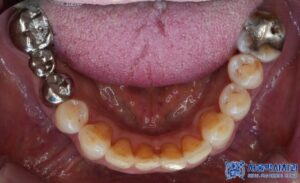

환자분은 좌측 아래쪽 어금니가 없는 상태였고,

오랫동안 방치되어 치조골(잇몸뼈)의

변화가 일부 있었습니다.

하지만 다행히도 임플란트를 식립하기에

충분한 골량이 유지되고 있었고,

무절개 방식으로 빠르게

임플란트를 진행할 수 있었습니다.

임플란트 치료 외에도, 환자분의 남아있는

치아들 중 심한 충치가 있는 어금니

(오른쪽 위 큰 어금니, 왼쪽 위 작은 어금니,

왼쪽 위 큰 어금니, 왼쪽 아래 큰 어금니)는

신경치료를 진행하였습니다.